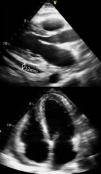

Em abril de 2008 inicia dor intermitente a nível escapular esquerda de características pleuríticas associada a tosse seca e astenia. Foi inicialmente considerado o diagnóstico de infeção respiratória, tendo cumprido dois ciclos de antibioterapia (azitromicina e levofloxacina) sem melhoria. A investigação do quadro incluiu nessa altura o ECG e o ecocardiograma transtorácico (ETT), que não revelaram alterações. Foi então assumida como uma dor de etiologia muscular, sendo realizado tratamento sintomático com paracetamol e anti-inflamatórios. No final de junho, houve agravamento das queixas álgicas e surgimento de febre. O exame objetivo não apresentava alterações relevantes. O ECG evidenciou um BIRD, má progressão da onda «r» de V1-V3 e ondas T negativas de V1-V5, previamente não existentes. Analiticamente foi detetada uma leucocitose (13.500/mm3) com 50% de eosinófilos (6.800/mm3, n < 400), uma elevação da IgE (515 IU/mL, n < 88); da troponina I (1,2 ng/mL, n<0,1); do BNP (158 pg/mL, nb < 100); e da PCR (321mg/dl, n<5). A radiografia (Rx) de tórax apresentava um pequeno derrame pleural esquerdo, sem alterações do parênquima pulmonar e com índice cardiotorácico aumentado. O ETT revelou cavidades cardíacas não dilatadas, boa função sistólica global e segmentar dos ventrículos esquerdo (VE) e direito (VD). As válvulas cardíacas não evidenciavam alterações morfológicas ou funcionais significativas. O pericárdio encontrava-se espessado, com derrame circunferencial médio (12mm na incidência paraesternal eixo longo), mas sem compromisso hemodinâmico (fig. 1). Foi internada com o diagnóstico de miopericardite em 14/07/2008. Iniciou tratamento com ácido acetilsalicílico em doses anti-inflamatórias e analgesia com derivados morfínicos, verificando- se uma melhoria da intensidade da dor. As análises revelaram redução dos valores de troponina i, da PCR e do BNP. O ETT documentou uma redução do derrame pericárdico, mantendo-se o pericárdio espessado. Por persistência da eosinofilia com valores anormalmente elevados, mesmo para os doentes com asma, e coexistência do derrame pleural esquerdo colocaram-se outras hipóteses de diagnóstico além de miopericardite aguda vírica: a) recidiva de TP, c) helmintose, d) síndrome hipereosinofílica, e) Churg-Strauss. O estudo analítico imunológico que incluiu ANA, ANCA e fatores reumatóides foi negativo; o exame direto da expetoração foi negativo para BK; a pesquisa em coproculturas de ovos, quistos e parasitas foi negativa. As serologias para o anticorpo (Ac) CMV IgM, Ac. EBV; Ac Herpes Simplex 1 e 2, Influenza A e B; Adenovirus; Echovirus; Coxsackie foram negativas. A TC torácica revelou um pequeno derrame pleural esquerdo. Teve alta no dia 16/07/2008 referindo apenas ligeira dorsalgia esquerda à inspiração profunda e medicada com ácido acetilsalicílico 1.000mg de 8/8h.

Dez dias após a alta reiniciou dor torácica, sem febre. O ETT de controlo demonstrou VD com hipocinésia do apex e uma massa apical de ecogenicidade idêntica à do miocárdio e sem plano de clivagem com a parede miocárdica (fig. 2). O pericárdio mantinha-se espessado e com derrame médio. Perante os novos achados equacionou-se a hipótese da massa do VD corresponder a um trombo, a um tumor ou representar uma massa secundária à síndrome hipereosinofílica. A doente iniciou anticoagulação oral com varfarina devido à suspeita de trombo e foi transferida para os Hospitais da Universidade de Coimbra para realização de ressonância magnética cardíaca (RMC) e biopsia endomiocárdica (BEM). A RMC revelou um marcado espessamento do miocárdio no apex do VD, com aspeto infiltrativo (fig. 3). No realce tardio observaram-se áreas de hipersinal de forma heterogénea no apex do VD, na parede septal e no apex do VE. Algumas destas áreas apresentavam uma distribuição sub-epicárdica. A BEM mostrou dissociação dos feixes musculares por eosinófilos, havendo destruição miocitária e necrose de coagulação, dados compatíveis com endomiocardite eosinofílica. Foi assim estabelecido o diagnóstico de endomiocardite de Löffler e iniciado tratamento com prednisolona oral, na dose de 1mg/kg/dia, mantendo a anticoagulação com varfarina. No seguimento registamos alívio completo da dor, normalização do valor de eosinófilos e desaparecimento do espessamento miocárdico do VD (fig. 4) confirmado pela RMC (fig. 5). A doente manteve anticoagulação durante 3 meses e corticoterapia durante 6 meses. Após esse período teve um episódio de dor dorsal mantida não acompanhado de hipereosinofilia ou alterações ecocardiográficas tendo realizado 4 semanas de corticoterapia. A doente tem tido consulta semestral onde realiza ECG, análises e ETT. Três anos depois do início do tratamento, e após a realização de outra RMC de controlo a doente encontra-se em remissão completa.